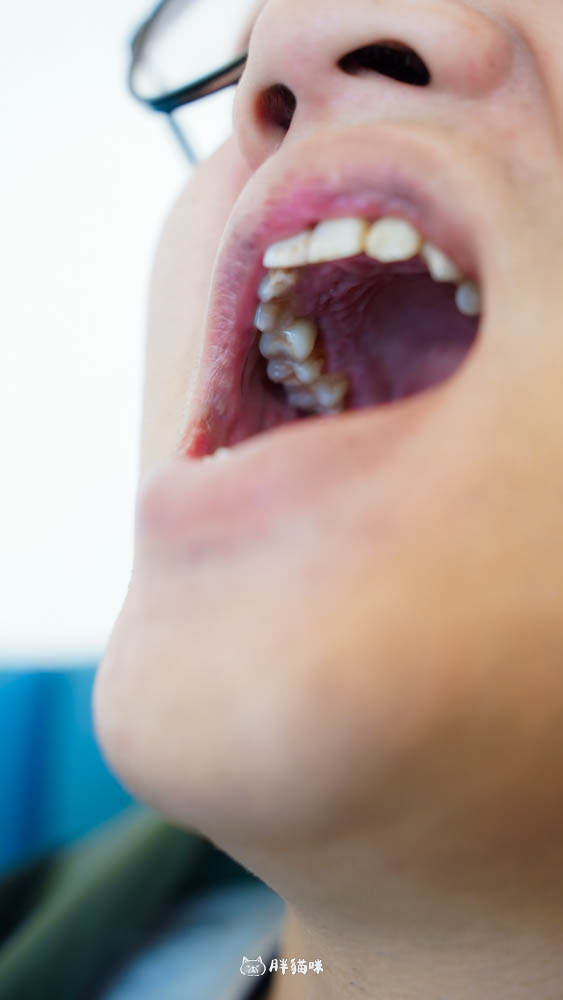

第三次(約三個月後):這是等骨整合完成後。因為這時候肉可能已經長出來包覆植體了,所以醫生會先開一個小洞,然後裝上一個小零件。接著,就要進行牙齒的 3D 掃描建模了,這一天我們也要來選牙齒的顏色!

掃描齒模體驗超酷~醫生不是用那種傳統、黏呼呼的印模材料!

而是讓萊肯躺在那邊,用一台機器在口內掃描,直接在電腦上生成3D 立體的齒模!這科技感,胖貓咪給 100 分。